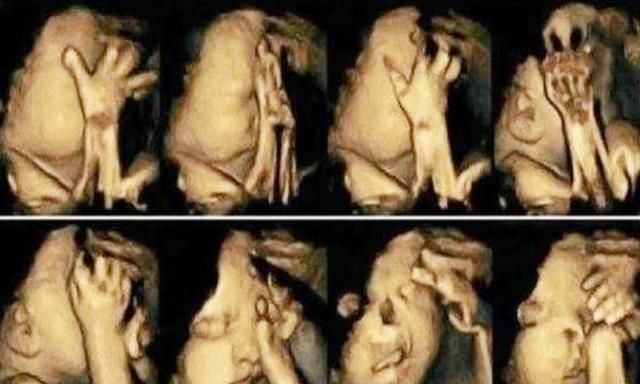

这个时候医生让小丽出去走一走,等孩子把正脸露出来再来复查,小丽出去走了一圈,回来检查时,屏幕上出现了孩子的正脸,正冲着屏幕“做鬼脸”呢。

小丽很高兴,医生却说这孩子不能要有明显的唇腭裂。医生解释到孩子多动不一定是好事,有可能是他不舒服。小丽却以为是孩子活泼的表现,现在还是存在着心理缺陷。医生建议小丽想清楚了,如果生下来就要做好做大手术的心理准备,还不一定能恢复到正常的面容。